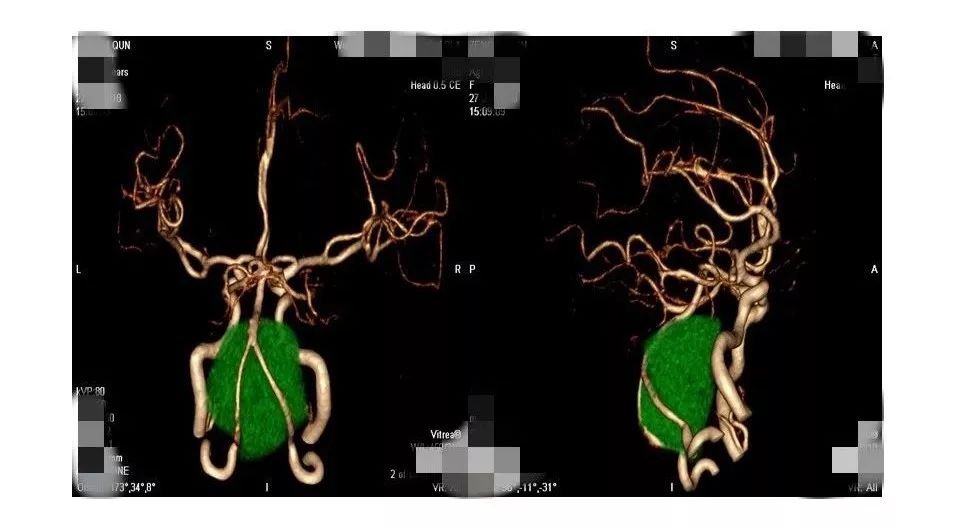

今天为大家分享的是《贝朗时间》第三十八期,由中国人民解放军武汉总医院神经外科副主任姚国杰教授带来的:远外侧入路全斜坡巨大脑膜瘤显微手术1例,欢迎阅读、分享!

远外侧入路全斜坡巨大脑膜瘤显微手术1例